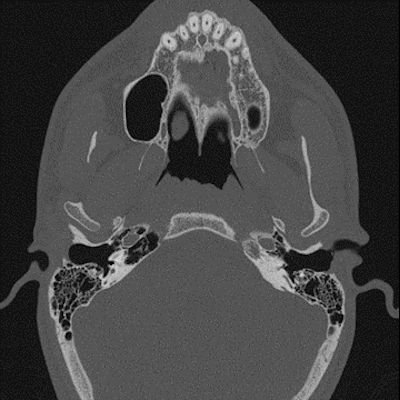

19 yaş, K

Kulakta dolgunluk, nefes sesini ve kendi sesini abartılı şekilde duyma

Tanınız nedir?